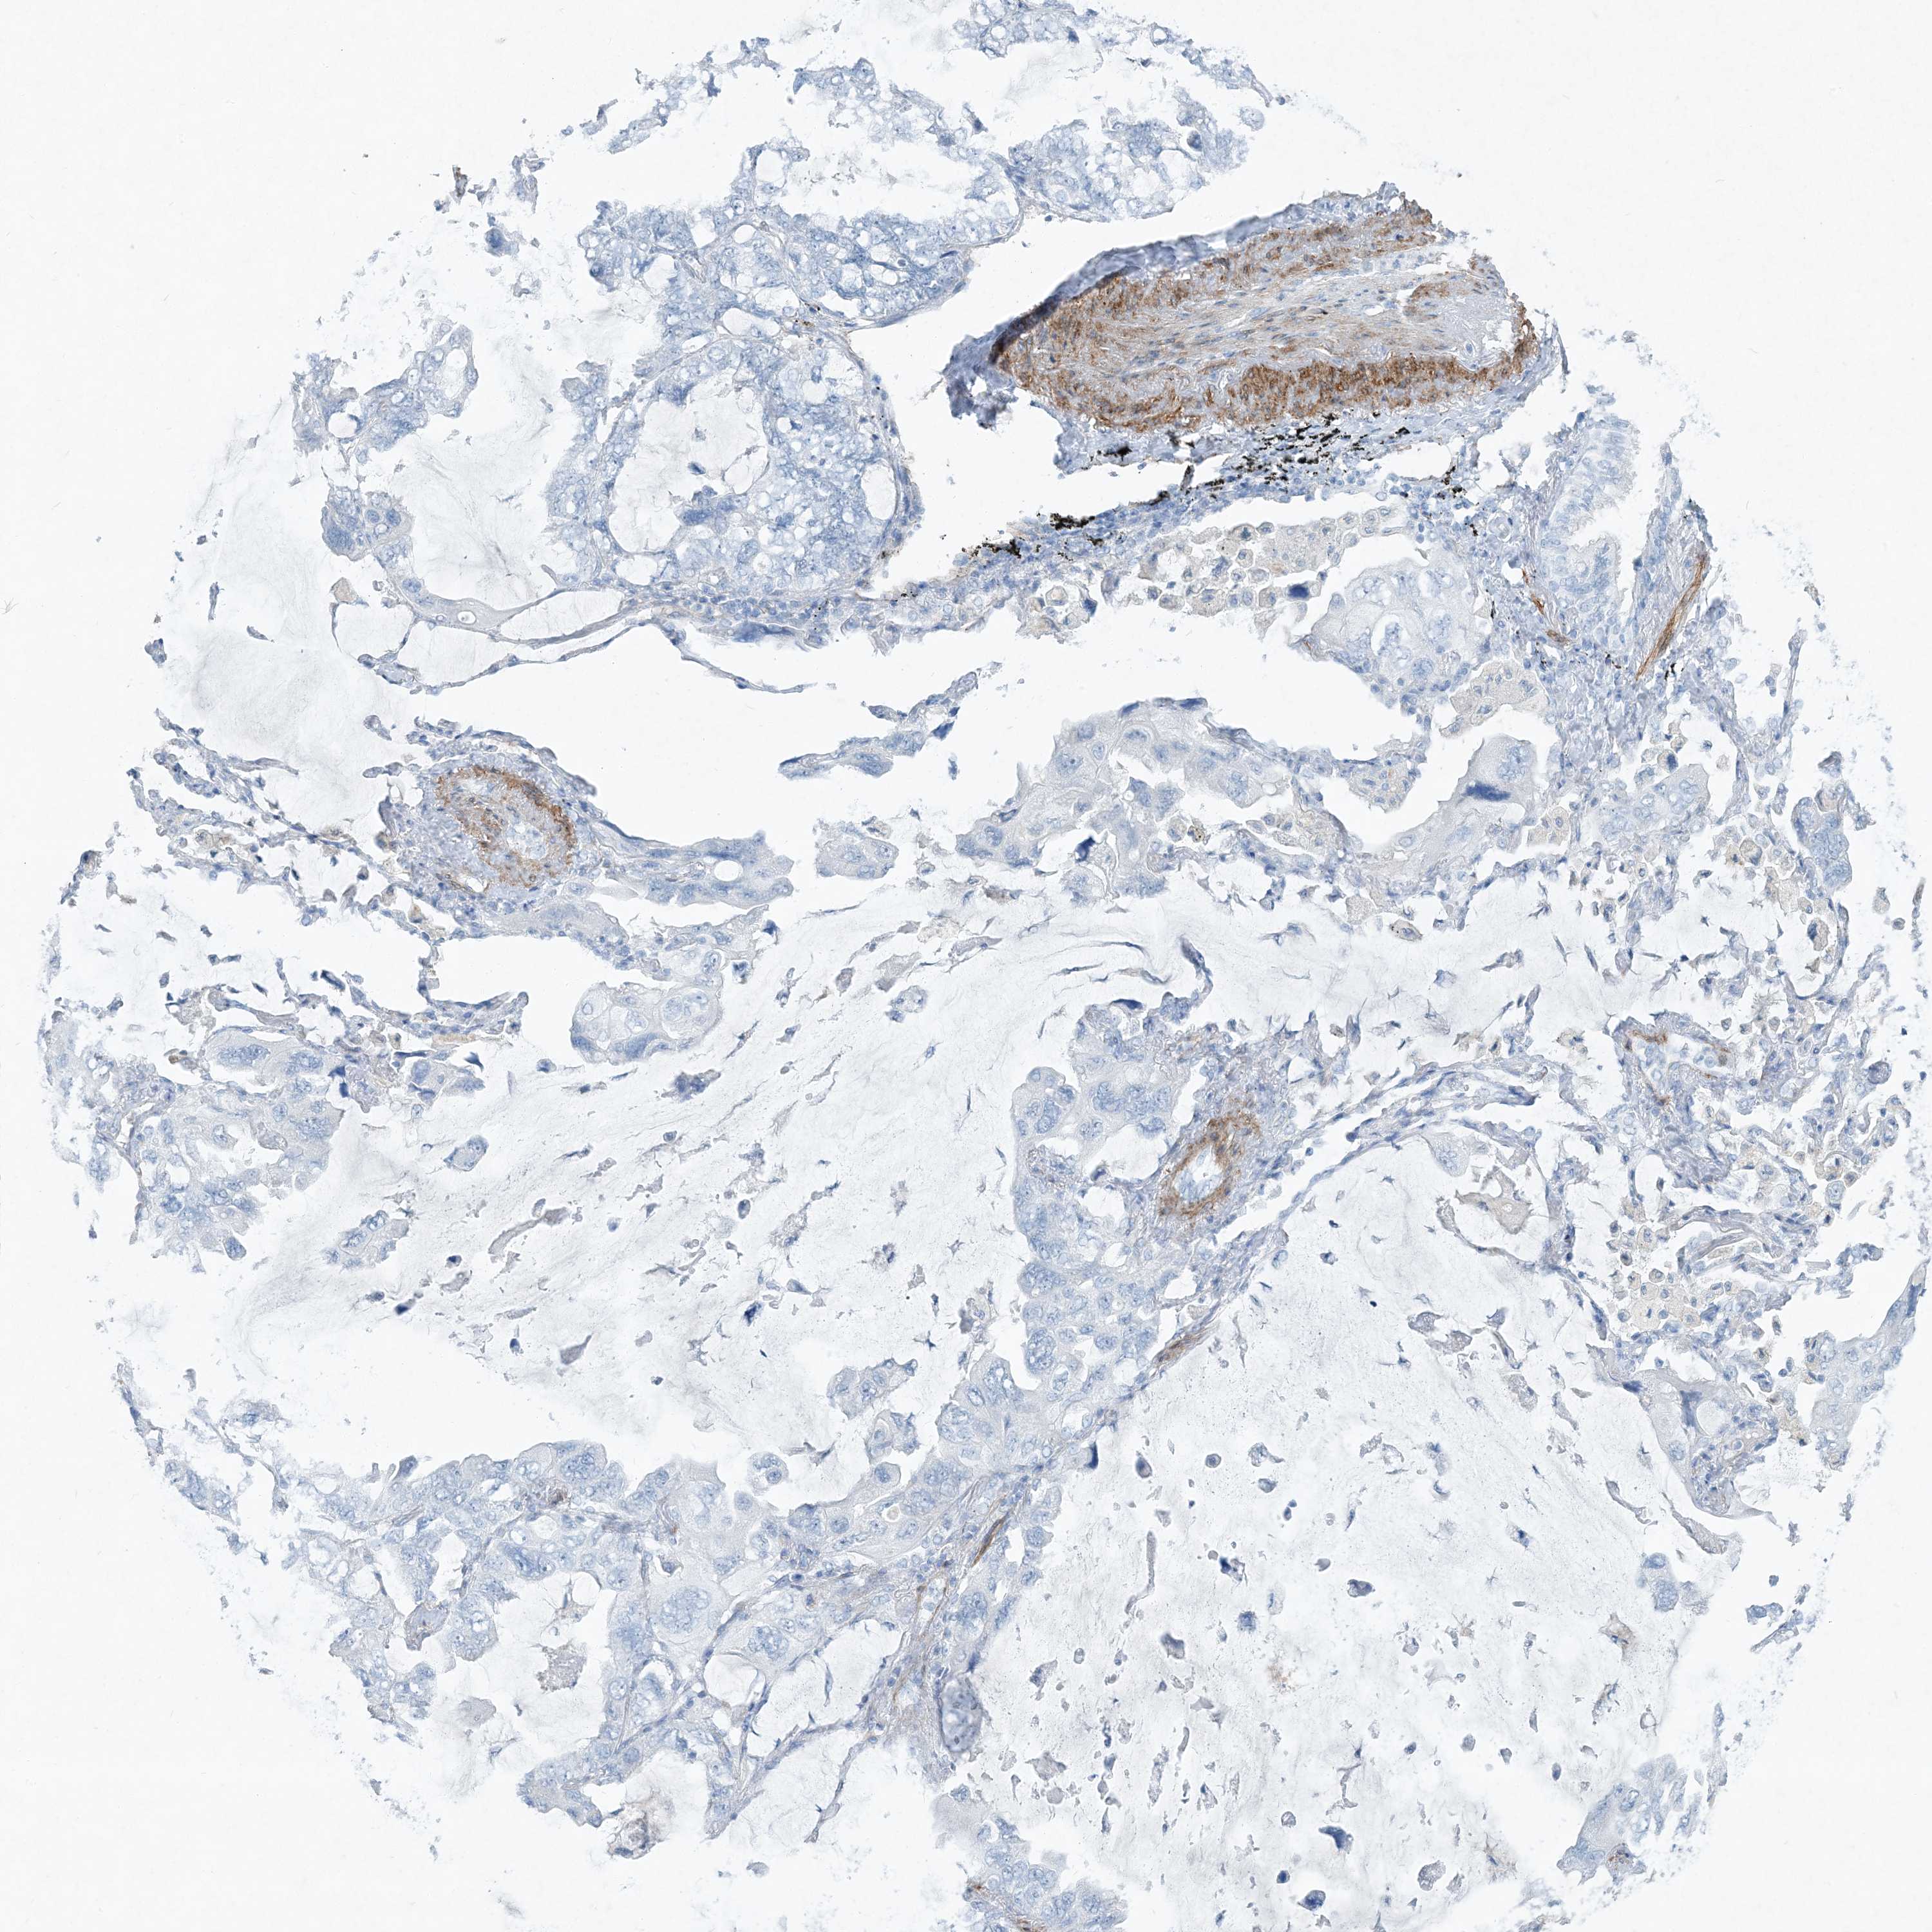

CANCER LUNG CANCER Show tissue menu

LUAD TCGA LUAD VALIDATION LUSC TCGA LUSC VALIDATION PROTEIN LUAD CPTAC PROTEIN LUSC CPTAC PROTEIN EXPRESSION